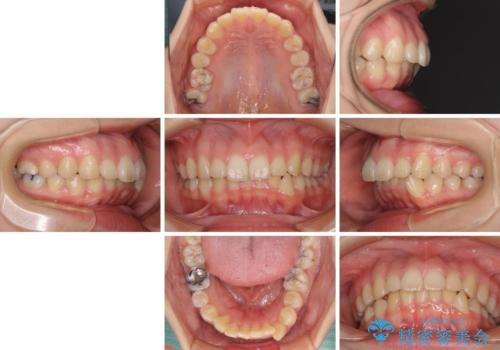

- 口元の突出感を気にして来院された患者様です。

上下左右の第一小臼歯4本を抜歯して口元を下げる治療計画としました。

目立たない装置が希望であったため、上顎が裏側装置である、ハーフリンガル装置を選択されました。

非常に大きな虫歯のあった下顎大臼歯は、根管治療を行い、矯正治療後にオールセラミッククラウンにて補綴治療を行いました。

当初予定では3年以上かかるとお伝えしておりましたが、スムーズに歯列が整い、2年強で終了することができました。